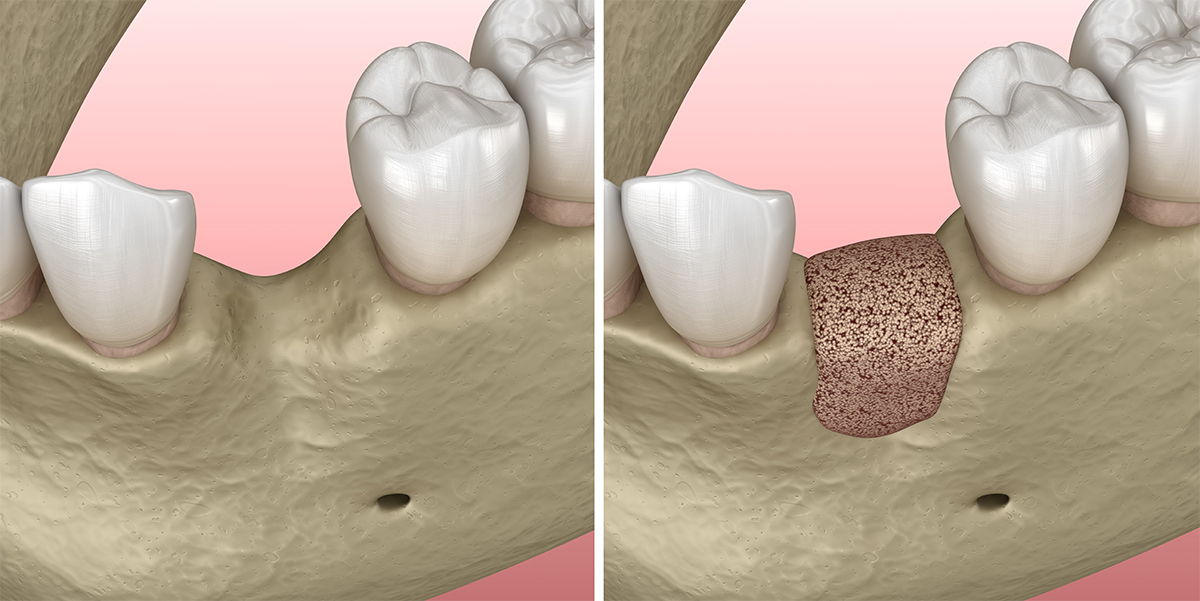

La greffe osseuse et la régénération osseuse sont des techniques chirurgicales permettant de restaurer l’os dans les zones où il a subi une perte significative. Ces interventions sont souvent nécessaires avant la pose d’implants dentaires, afin de garantir un support solide et une intégration optimale.

Lorsque des dents sont extraites, l’os qui les soutenait peut progressivement perdre en densité et en volume. Dans certains cas, cette résorption osseuse empêche la mise en place d’un implant, notamment lorsque des obstacles anatomiques comme le sinus maxillaire ou le nerf alvéolaire inférieur limitent l’espace disponible.

La greffe osseuse permet alors de recréer une base osseuse suffisante en augmentant la largeur et/ou la hauteur de l’os, garantissant ainsi une pose d’implant dans de bonnes conditions et en toute sécurité.

- Intervention chirurgicale sous anesthésie locale : la greffe est positionnée au niveau du défect osseux.